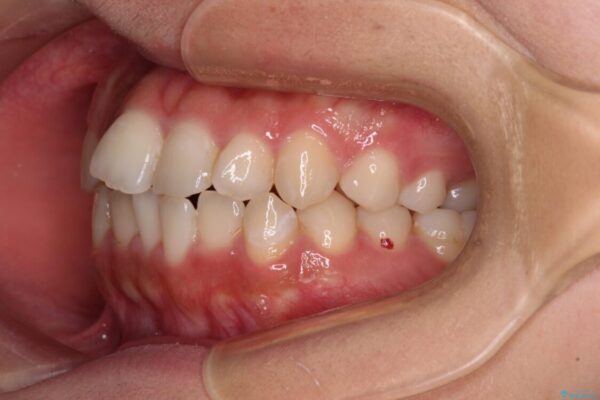

治療後

• 【モニター】短期間で終わりたい ワイヤー装置での非抜歯矯正 治療後画像